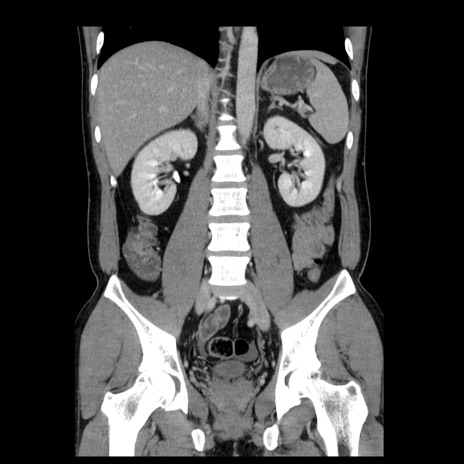

症例4(冠状断像)

【症例】30歳代男性

【主訴】腹痛、嘔吐

【現病歴】昨晩から突然の腹痛あり、その後嘔吐、軟便も出現。腹痛が改善しないため救急搬送となる。2日前にしめ鯖の食事歴あり。

【身体所見】意識清明、苦悶様、BP 135/90mmHg、BT 35.7℃、腹部:平坦、やや硬、心窩部〜臍部に自発痛、圧痛あり、筋性防御+、反跳痛-

【データ】WBC 8100、CRP 0.57